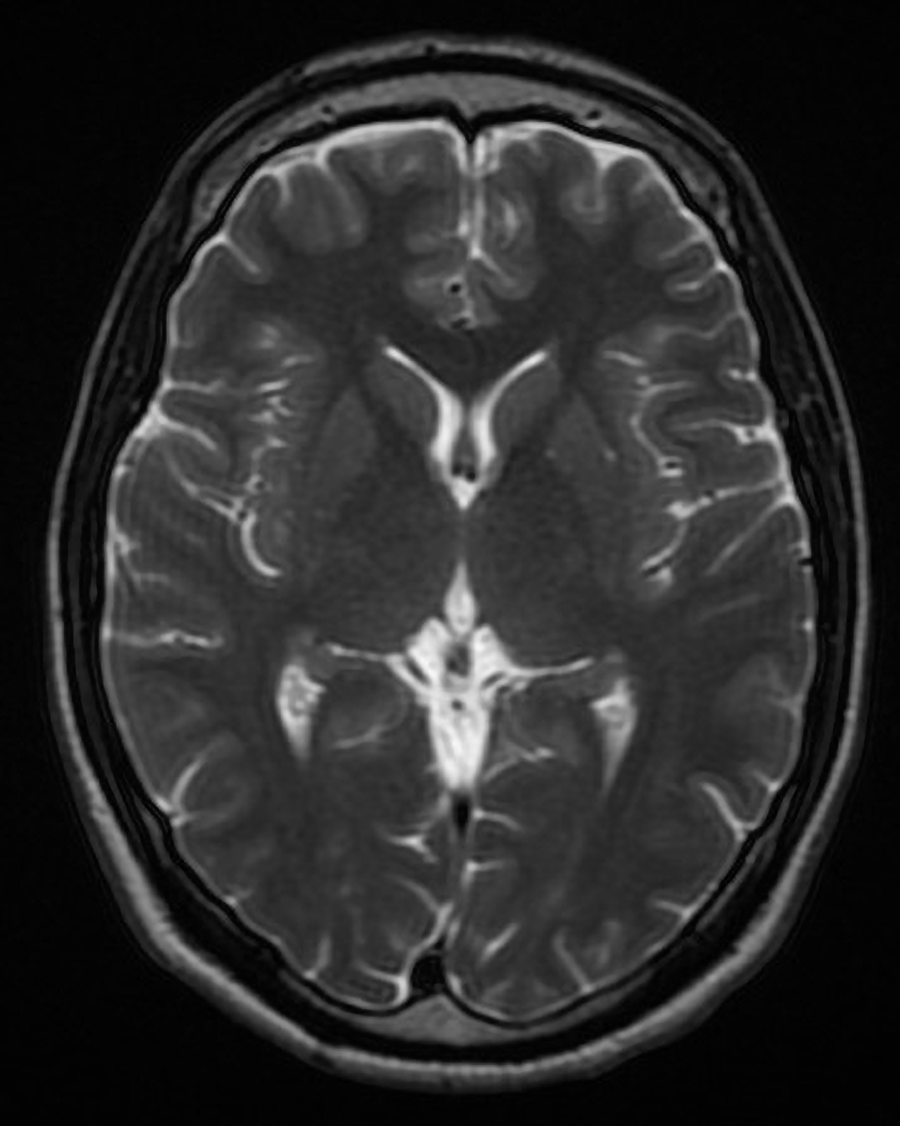

The images produced by MRI scans differ in signal intensity. Hyperintense regions are bright on MRI. Hypointense regions appear dark on MRI. As you learned previously, MRIs can produce T1-weighted images or T2-weighted images. T1 hyperintense regions can represent fat, hemorrhage, and similar structures. T2 hyperintense regions can represent edema, fluid, inflammation, and similar structures.

A T2-weighted MRI of the brain.